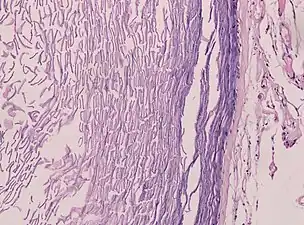

Un kyste épidermique ou kyste à inclusions infundibulaire est un kyste bénin que l’on retrouve sur la peau. Le kyste se développe à partir du follicule pileux. Histologiquement, il est constitué d'une fine couche d'épithélium malpighien.

Les kystes épidermiques sont généralement diagnostiqués lorsqu'une personne remarque une bosse sur la peau et consulte un médecin. Le diagnostic définitif est posé après exérèse, par un médecin pathologiste sur la base de l'aspect microscopique d'une lésion kystique bordée d'un épithélium malpighien contenant de la kératine lamellaire[5]. Ils peuvent également être observés sous forme de lésions isointenses en IRM ou d'hyperintensités en FLAIR.